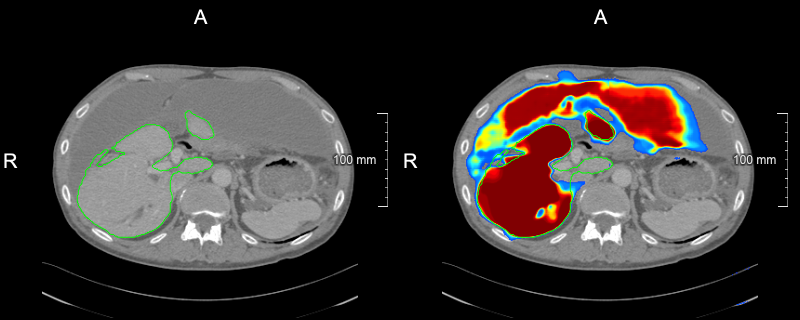

(a) slice-level uncertainty: 0.0660.0660.066

Refer to caption

(b) slice-level uncertainty: 0.0560.0560.056

(c) slice-level uncertainty: 0.0520.0520.052

(d) slice-level uncertainty: 0.0200.0200.020

Figure 2: Examples of slices selected in the first USS iteration with overlaid liver reference segmentation (green contour) and model liver probability output (heatmap): (a)-(c) slices with the biggest slice level uncertainty, (d) slice with the lowest uncertainty among selected ones.

As our strategy relies on the model’s uncertainty to query cases, the confidence calibration of a model can have a substantial impact on which cases are deemed uncertain. Recently, it has been shown that modern deep neural networks do not output well-calibrated probabilities and tend to be overconfident[28]. In our work, we have used MC dropout that improves the calibration quality of models trained with the Dice loss[22]. Exemplary probability maps produced by our model are shown in Fig. 2. We think that investigation of various calibration techniques, e.g., deep ensembles and temperature scaling, in the context of active learning could be an interesting future research direction.